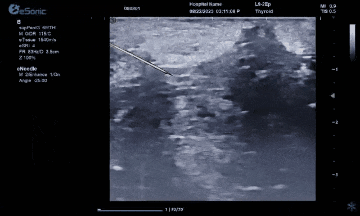

而准台式RTE弹性成像在超声介入应用中又是一大助力。操作简单、高实时性高重复性、通过颜色可直观评评估组织软硬程度。也有助于非肿块区域硬度异常的发现和评估。在穿刺中可引导穿刺到硬度较大的区域,提高穿刺阳性的成功率。

智能介入解决方案、无磁导航,可以在比较复杂的环境中,如ICU、其它床旁等场景下应用时,不会受周围机器的影响。另外,除了常规的穿刺针智能增强,支持针体增强程度调节外,智能穿刺针彩色Map技术又是新航娱乐医疗(ESI)准台式超声的首创技术。在超声引导穿刺消融的过程中,能够增强穿刺针与组织的对比度,清晰显示针尖与针体。